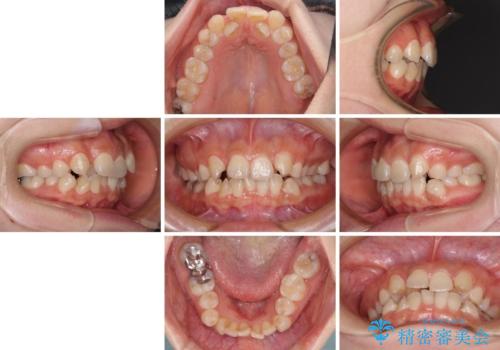

- 前歯の著しいデコボコを気にして来院された患者様です。

上顎の左右側切歯(前から2番目)が裏側に隠れいてる状態で、咬み合わせや清掃性に大きな問題が認められました。

左下に八重歯があったそうですが、当時は矯正治療を行うことを考えていなかったため、抜歯してしまったとのことでした。

叢生が著しいため、左下以外の第一小臼歯3本を抜去し、目立たないワイヤー装置にて矯正治療を行うこととしました。